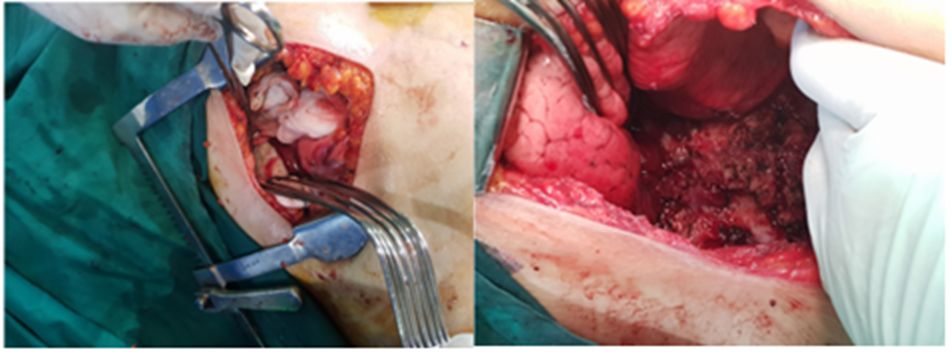

A 58-year-old woman was refered to our hospital with a history of recurrent right side chest wall pain ,cough ,night sweating ,hemoptysis and dyspnea for 4-6 weeks. A physical examination revealed respiratory sounds were decreased on the middle right side of chest. His complete blood count, erythrocyte sedimentation rate, CRP blood urea nitrogen (BUN) level, and creatinine level were normal and liver function tests (AST,ALT ,AKP and bilirubin ) and anti hydatid tests were normal . Poster anterior (PA) and lateral chest radiographs were performed . The PA chest radiograph (Figure 1)showed a well-defined 10- to 14-cm right paracardiac cystic mass located in the right middle zone of chest. The CT-scan showed a large well –defined hypo dense cystic mass measuring 112 mm is seen in superior segment of RUL.Sub segmental atelectasis also seen in right lung caused compressing. Left lung was normal . Figure 2(a,b,c,d,e,f,g,h,i) . In the CT –scan there was no invasion of the chest wall and others intrathoracic structures. CT images show no enlargement of lymph nodes and pleural effusion but lung parachymal was involved.The testes for hydatid cyst were negative .Ultrasonography of abdomen was normal . A classic right posterolateral thoracotomy in six intercostal space was performed. Around of cystic lesion was walling off with wet sponge with normal Saline (Fig 3). In the aspiration of the lesion there was a hemorrhagic dense viscous fluid .The cystic mass was completely removed without complications and free margin. On the operation time , macroscopic examination show hemorrhagic dense viscous fluid and debris was observed in the center of the lesion(Fig 4) Microscopic examination showed an encapsulated mesenchymal neoplasm composed of short fasciles of bland looking spindle cell which are diffusely positive for S100 and GEAP on immunohistochemically diagnosis was a schwannoma tumor. The patient was discharged on the 6 th postoperative day. The patient did not recurrence after 8 month of follow-up

Figure: 3- A, B, C, D show walling of aroun cystic lesion for prevention of spillagechstic fluid and debris of cystic masses.